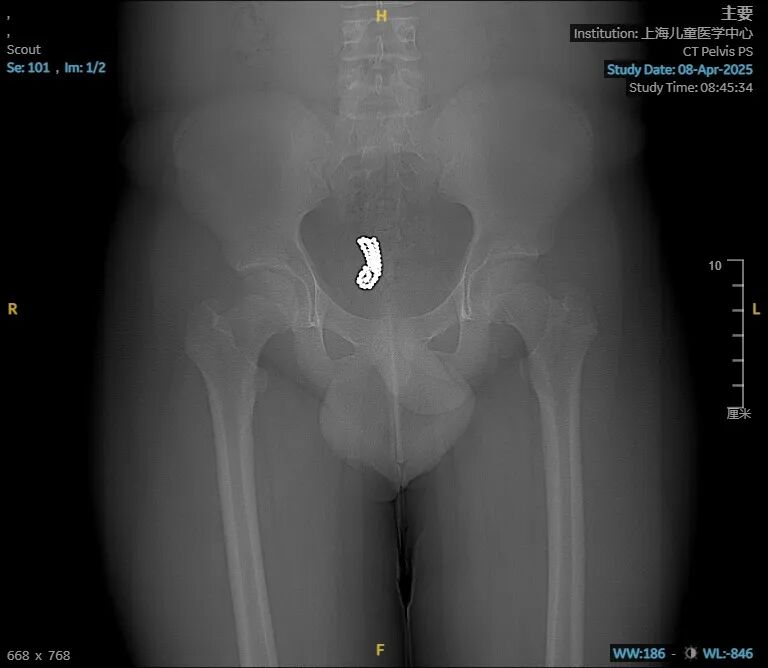

据此前报道,一名14岁男孩把整整52颗珠子从尿道塞入自己的膀胱。

这名少年患者因青春期好奇心驱使,自行将52颗直径约5毫米的珠子经尿道塞入膀胱。4天后,出现了排尿困难、下腹疼痛等症状,在家人的陪同下前往医院就诊。

CT影像显示,这些珠子全部沉淀在膀胱最下端,不仅造成尿路梗阻,更可能因持续压迫导致膀胱黏膜损伤。